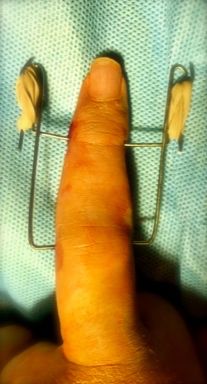

También puede aparecer fracturas de la base de F2, consecuencia de un traumatismo. Dependiendo el tamaño del fragmento, puede aparecer subluxación de la articulación por lo que habrá que realizar una reducción cerrada. La tracción mantenida mediante un fijador externo evita el colapso de la articulación y mantiene la congruencia articular (Figura 21).

Figura 21: a- fractura base F2 intraarticular con subluxación articular y b,c- tratamiento quirúrgico mediante técnica de Suzuki.